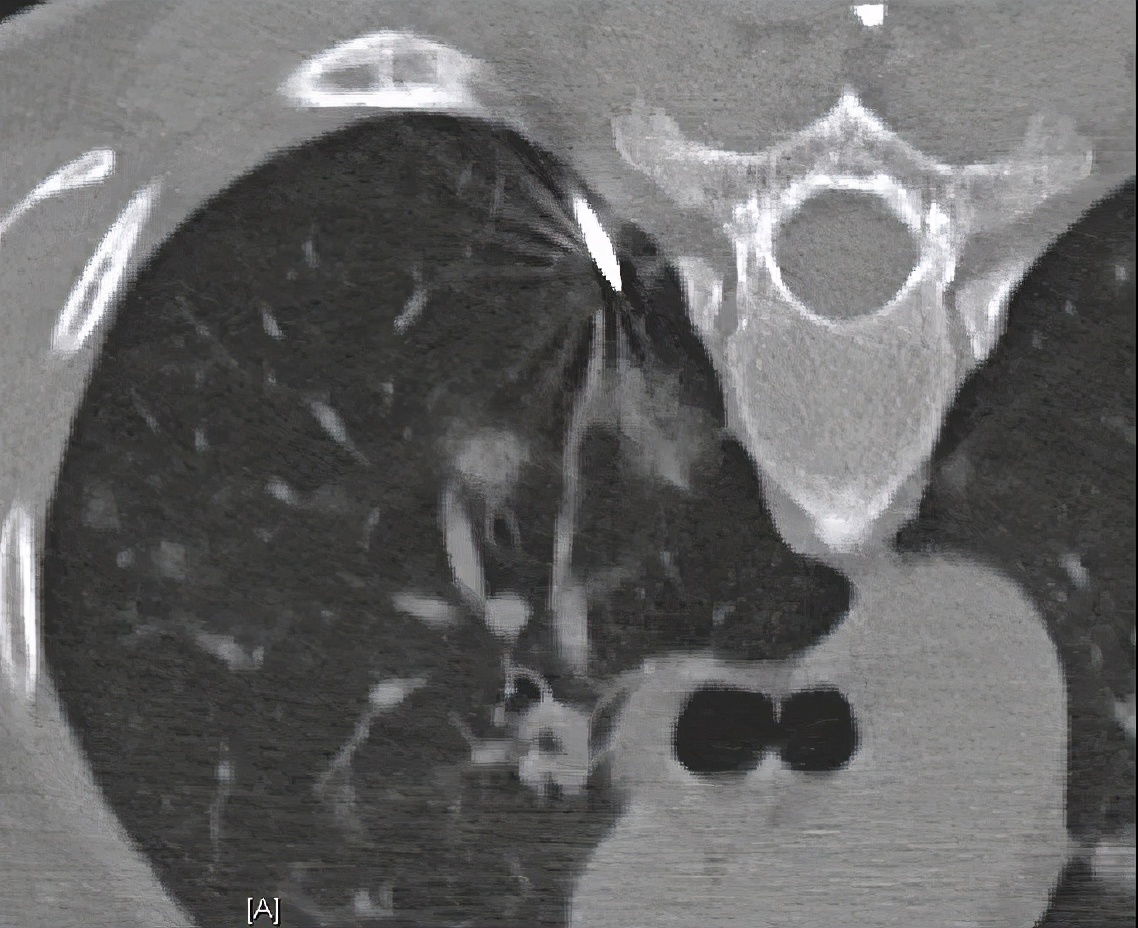

胸部CT(2019-08-19):右下肺新发炎症病变;余两肺炎性病变,较前相仿。

该病例真是一波三折,目前机化性肺炎诊断明确,停药后进展,进展后加用硫唑嘌呤。目前阶段出现右下肺新发病灶,和前面影像学表现不同。这次病灶靠近胸膜下、实变、支气管充气征,周围有晕征改变,结合T-SPOT,考虑结核感染。但本病灶位置并不是结核好发部位,虽然G和GM试验阴性,但也不能完全排除真菌性感染,此时需要借助侵袭性方法进行微生物培养,更有利于下一步更精准治疗。

何礼贤教授

我同意李教授的分析,这个病人诊断明确,是隐源性机化性肺炎,激素治疗约8月,目前右下肺出现新病灶,与之前病灶特征不同。另外,此机化性肺炎的影像学特点和通常看到的隐源性机化性肺炎不同,通常我们看到的隐源性机化性肺炎多为游走性的实变影,该患者闭塞性支气管炎的特征比较明显,支气管壁的增厚、扩张、扭曲,肺实质病变和炎症、小叶中央型小结节也存在,是闭塞性支气管炎伴机化性肺炎,这种表型比较少,可增加深呼吸相胸部CT协助诊断。此患者免疫抑制,免疫力低下,社区发病,有文献报告免疫力低下CAP和普通CAP病原体谱相同,但根据患者影像学特点和治疗反应,要注意特殊病原体感染。免疫抑制患者并发结核有两种情况:继发性肺结核,原来就存在潜伏肺结核,免疫力低下时复发;该病人我还是考虑原发性肺结核。